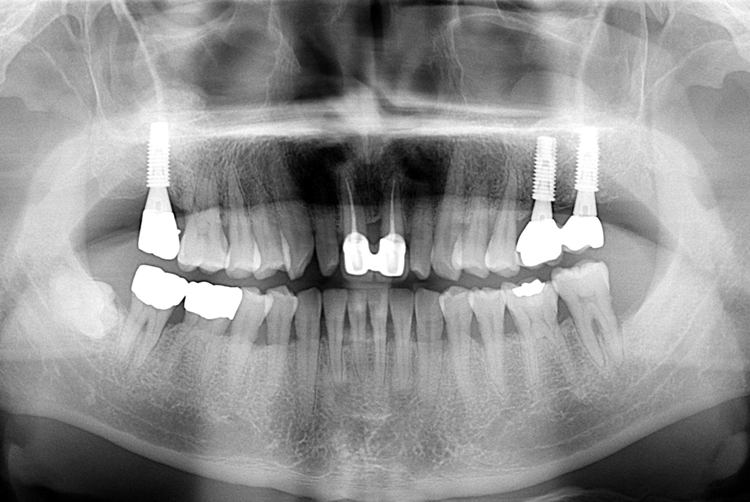

[임플란트] 어금니 임플란트

치료후 : 2017-12-07

세종치과는 많은 환자와 다양한 케이스를 바탕으로

항상 편안한 임플란트 수술을 제공하고자 노력하고,

오래동안 튼튼히 쓸 수 있는 임플란트 수술을 가장 큰 목표로 삼고 있습니다.